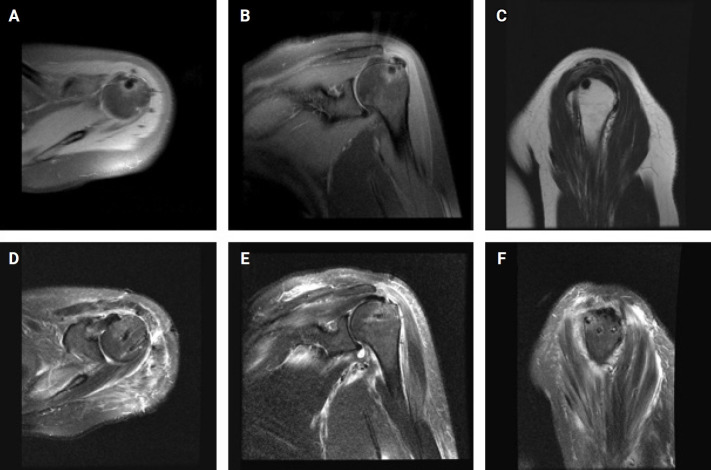

We present a case of calcific tendinitis in the shoulder, where calcifications were observed within both the tendon and the adjacent bone. At the time of acute onset, radiographs (including a plain radiograph) and magnetic resonance imaging revealed calcific tendinitis with intraosseous migration. The patient's symptoms did not improve after 5 months of conservative treatment. The patient underwent arthroscopic debridement of the calcific deposits, and the defect was repaired using the double-row repair technique. The patient's symptoms improved 3 months after arthroscopic treatment. We share our unusual experience with arthroscopic debridement in the treatment of chronic calcific tendinitis with intraosseous migration.